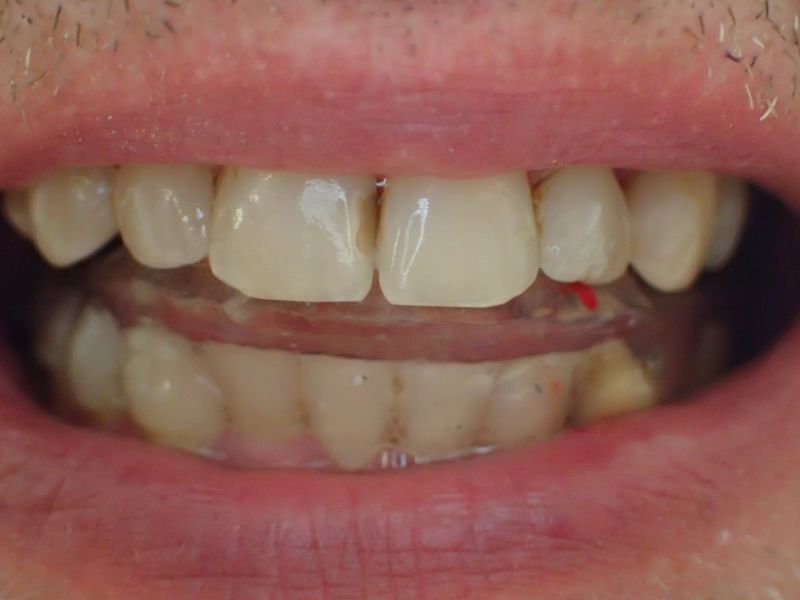

2. Herstellung und Eingliederung eines adjustierten Aufbissbshelfs

Erkennbar ist die massive Abweichung der habituellen Bisslage von der neuromuskulär zentrierten Bisslage.